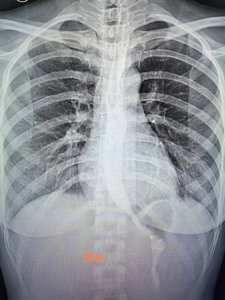

近日,她找到我院消化内科主任张宝华主任医师就诊,张主任详细了解病史后,为她完善了食道吞碘造影检查,结果显示食道贲门变窄呈“鸟嘴征”,造影剂通过受阻,考虑食道贲门失弛缓症,行胃镜检查不排除贲门失弛缓症。结合病史及辅助检查,陈女士被确诊为贲门失弛缓症。

今年1月下旬,在患者及家属知情同意后,麻醉科团队密切配合,由张华宝主任医师带领指导内镜手术团队,谭巧玫副主任医师经过1个多小时的努力,成功为陈女士完成POME手术。术后第二天陈女士可以流质饮食,长期困扰她的吞咽困难症状消失,Eckardt评分0分。复查食道吞碘造影提示造影剂顺利通过贲门进入胃内,恢复良好,目前已康复出院。